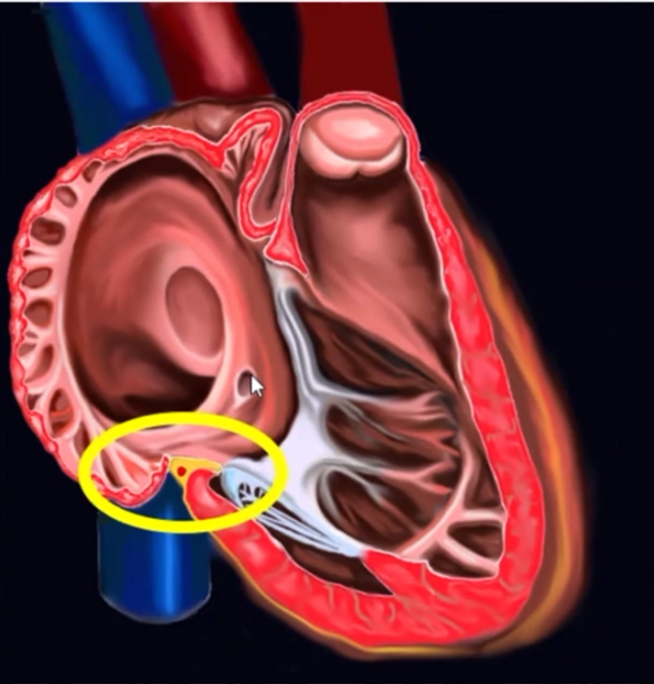

ICE-相对平坦的三尖瓣峡部

连接凹陷两端的肌束

超声观察到右冠状动脉

比较长的三尖瓣峡部

峡部边界

三尖瓣环,下腔静脉口,冠状窦口组成峡部。

三尖瓣环与下腔静脉口之间的峡部最窄,是消融最重要的经线。